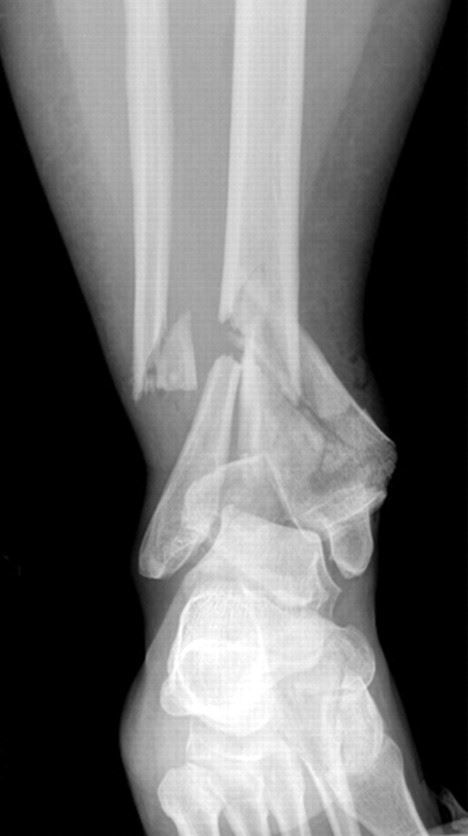

En esta radiografía de tobillo, la tibia y el peroné están fracturados. Las piezas de hueso están marcadamente fuera de lugar.

Reproducido de Crist BD, Khazzam M, Murtha YM, Della Rocca GJ: Pilon fractures: advances in surgical management. J Am Acad Orthop Surg 2011; 19: 612-622.

Los huesos, las calcificaciones, algunos tumores y otra materia densa aparecen en color blanco o claro debido a que absorben la radiación. Los tejidos blandos menos densos y las fracturas en los huesos permiten que la radiación los traspase, lo que hace que estas partes se vean más oscuras en la película de rayos X.